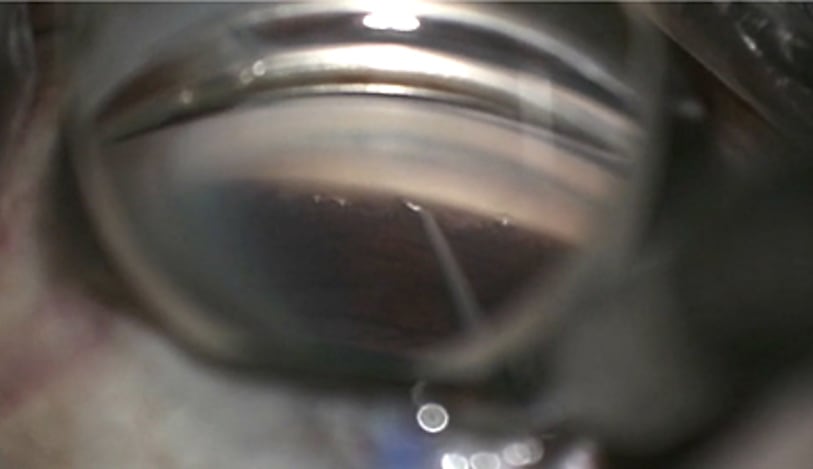

Glaucoma Group Therapy Video: Complications in Canaloplasty